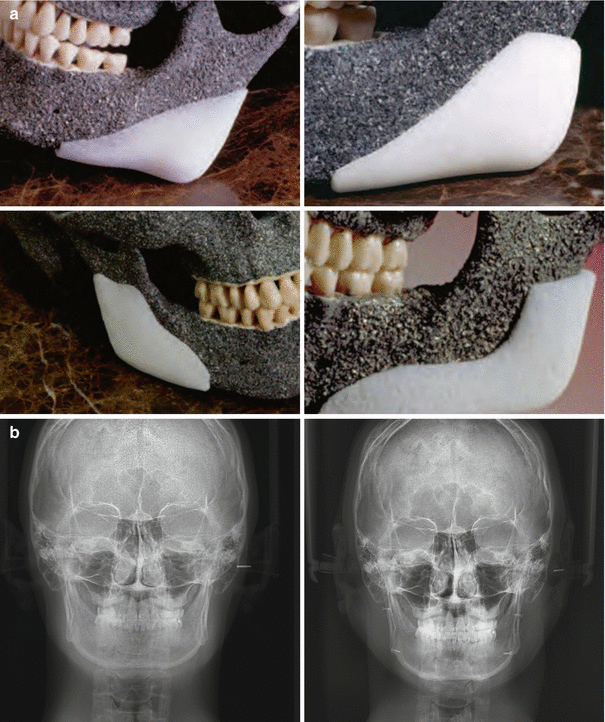

Fig. 13.3

Various ready-made Medpor® implants suited for the mandibular angle. (Lower left) preop x-ray, after insertion of medpor implant and fixation with screws